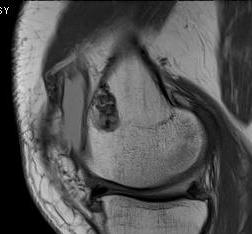

MRI

Can be very difficult to distinguish between low grade chondrosarcoma / atypical cartilaginous tumour and enchondroma

Enchondroma versus chondrosarcoma

- enchondroma versus grade 1 chondrosarcoma

- correct diagnosis enchondroma xray 67% and MRI 58%

- correct diagnosis chondrosarcoma xray 21% and MRI 58%